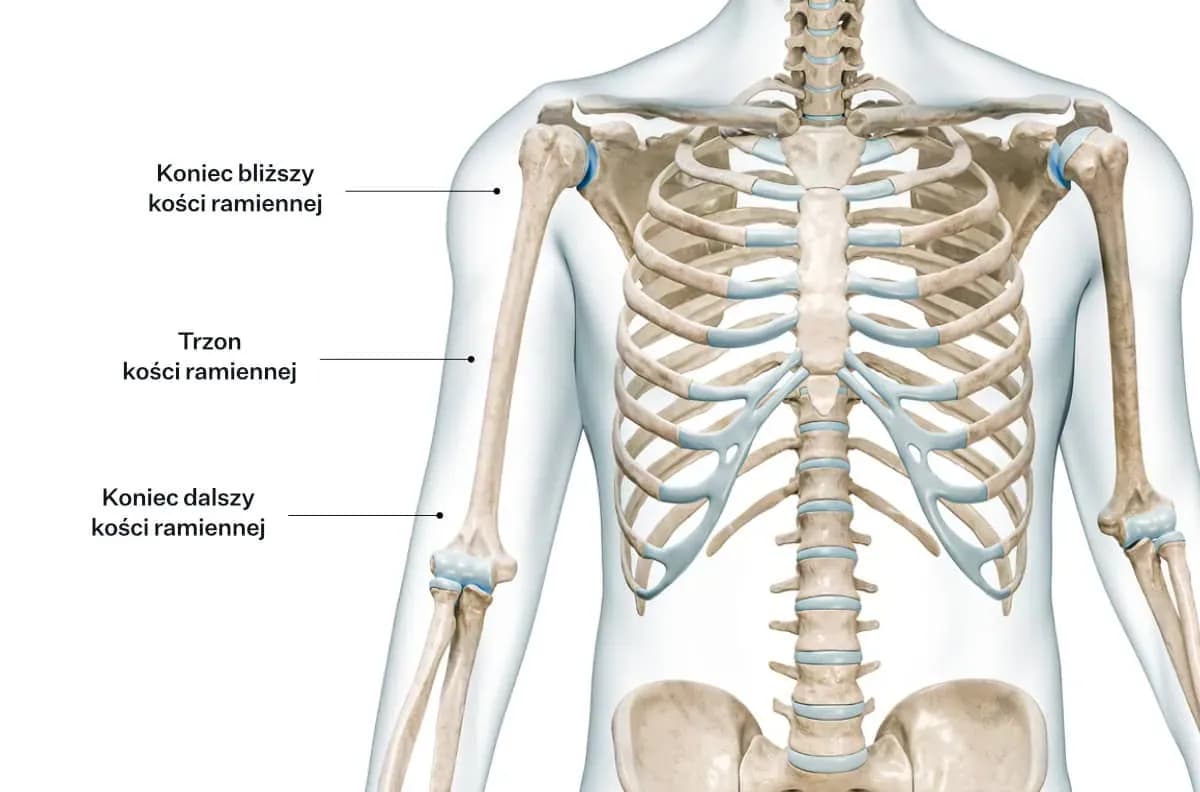

Zdecydowanie tak. Rodzaj i lokalizacja złamania to jedne z najważniejszych czynników wpływających na długość i złożoność rehabilitacji. Złamania nasady bliższej kości ramiennej, czyli te w okolicy barku, często są bardziej skomplikowane ze względu na bliskość stawu i dużą liczbę mięśni. Złamania trzonu, czyli środkowej części kości, mogą goić się inaczej, a złamania w okolicy stawu łokciowego również mają swoją specyfikę. Złamania wieloodłamowe, gdzie kość rozpadła się na wiele części, czy te z dużym przemieszczeniem, wymagają znacznie dłuższego leczenia i intensywniejszej rehabilitacji niż proste, stabilne pęknięcia.